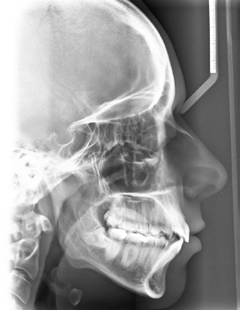

Die Patientin stellte sich im Alter von 23 Jahren zu einer kieferorthopädischen Beratung vor. Sie störten die Engstände im Unterkieferzahnbogen. Die extraoralen Aufnahmen zeigen ein schönes, harmonisches, leicht konvexes Profil, das nach den Grundregeln der Ästhetik nicht verändert werden darf (Abb. 18a bis c). Die intraoralen Aufnahmen zeigten zu Behandlungsbeginn eine Angle-Klasse-I-Okklusion, Tendenz zu Klasse III rechts und Klasse I links. Auf der Frontalaufnahme ist die knappe sagittale und vertikale Frontzahnstufe zu sehen (Abb. 19a bis c). Im Rahmen der Modellanalyse konnte eine harmonische Breitenrelation beider Zahnbögen im Bereich der Molaren und Prämolaren ermittelt werden, im Oberkiefer waren die Platzverhältnisse ausgeglichen. Im Unterkiefer lag ein Engstand von insgesamt 5 mm vor, wobei sich die Engstände auf die Frontzahnregion konzentrierten (Abb. 19d und e). Das angefertigte OPG (Abb. 20) zeigte, dass alle Zähne vorhanden und die Zähne 38 und 48 retiniert und verlagert waren. Im Seitenzahngebiet war eine konservierende Versorgung zu verzeichnen. Die parodontale Situation war röntgenologisch sowie klinisch unauffällig und die Knochenverhältnisse ließen eine orthodontische Behandlung zu. Die Fernröntgenaufnahme (Abb. 21) zeigte keine skelettalen Auffälligkeiten. Die Oberkieferfront stand nahezu achsengerecht, die Unterkieferfront war nach labial gekippt (Tab. 3).

Um die Okklusion in der vertikalen Dimension zu kontrollieren und den knappen Überbiss nicht zu verlieren, wurden zwischen den oberen Eckzähnen einerseits und den unteren Eckzähnen sowie 1. Prämolaren andererseits up & down-elastics in Form eines Dreiecks eingehängt. In den später eingegliederten Stahlbogen wurde zudem eine entsprechende Extrusionsstufe für die Oberkieferfront eingearbeitet. Die Zahnbögen waren lückenlos ausgeformt und nivelliert. Im Seitenzahngebiet war die Okklusion auf Klasse I eingestellt, die Frontzahnstufe war in sagittaler und vertikaler Richtung physiologisch (Abb. 25a bis e). Es trat keine Profilveränderung ein (Abb. 26a bis c). Die Parameter der Fernröntgenaufnahme (Tab. 3) lassen die dentalen Veränderungen erkennen; aufgrund der Zahnhartsubstanzreduktion kam es zu einer vergleichsweise geringen labialen Kippung beider Fronten. Zur Retention wurde an den Ober- und Unterkiefereckzähnen ein Retainer fixiert. Zusätzlich wurden im Ober- und Unterkiefer Retentionsplatten eingesetzt.